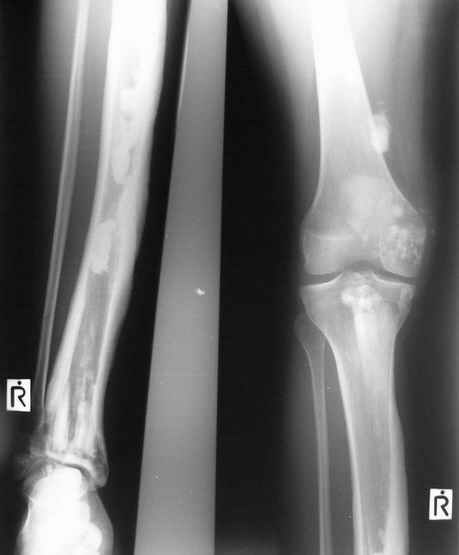

Уажаемые коллеги,представленные рентгенограмммы я показывал на нашем х-рей митинге - они были встречены с большим интересом.. Ну, ещё бы - я сам эту патологии встречал раза три за всю свою долгую жизнь:

После меня выступал с новыми находками для своей коллекции Эмануэл Лакью Тесема, хирург-ортопед из Эфиопии: Мне понравились его находки:

Кто шустрый - при какой патологии встречается так называемые "суставы Шарко"?Второе приобретение доктора Эмануэла мне понравилось своим романтическим названием: Candle bone - <кость-в-виде-оплывающей-свечи> : Просто редкая патология:

VR>Второе приобретение доктора Эмануэла мне понравилось своим романтическим названием: Candle bone - <кость-в-виде-оплывающей-свечи> : Просто редкая патология:

Мелореостоз

Под названием "мелореостоз" описано около 50 случаев врожденного заболевания скелета, выражающегося в совершенно

своеобразном одностороннем остеосклерозе костей одной только конечности. Можно не сомневаться в том, что

мелореостоз встречается далеко не редко; мы наблюдали свыше 20 случаев. Вполне естественно, что отдельные новые

казуистические наблюдения, не вносящие в науку никаких новых фактов и не возбуждающие новых мыслей и обобщений,

остаются неопубликованными.

Остеосклероз при этом заболевании захватывает не всю кость по окружности, а простирается слегка волнистой

полосой вдоль длинной оси конечности (рис. 223, К), переходя через линию суставов на другие кости. Таким образом,

может оказаться пораженной целая верхняя или нижняя конечность или больший или меньший ее периферический участок,

например, часть лопатки, полуцилиндр плечевой кости, часть цилиндра лучевой кости и скелет II пальца вместе с

лежащими по этой оси участками запястных костей или же часть - медиальная или латеральная - бедренной,

болынеберцовой кости с продолжением и расширением процесса на предплюсневые и плюсневые кости и соответствующие

по длиннику фаланги одного или нескольких, но никогда не всех пальцев. Описавшие эту болезнь в 1922 г. Жоани

(Joanny) и Лери (Leri) сравнивают остеосклеротические полосы с картиной, напоминающей стекающий со свечи и

застывающий стеарин или воск, отсюда и название "мелореостоз" - "стекающая вдоль конечности кость".